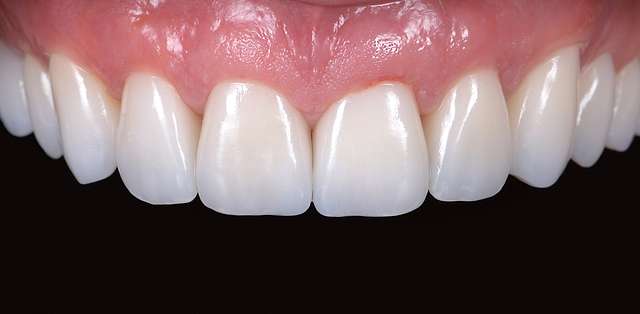

A gingival graft is a micro-surgery that will transplant a bulk of soft tissue - free gingiva or connective tissue ( the internal layer of gingiva ) to cover a soft tissue defect. Usually this type of procedures is required to augment implants, or to cover defects caused by periodontal disease or trauma. The grafts are harvested from the third molar region or the palate, and are transported where they are needed.

This type of procedure is a very delicate one, using the same type of blades like the ones used in ophthalmology and the sutures are also very thin. The sutures will be removed after 7-14 days, depending on the case, when primary healing is achieved. The maturation of the graft will take roughly 90 days, this is the reason why, when placing implants we prefer to also do the graft, so we can sync the healing time for both procedures.

Using tissue grafts to correct tissue defects

Using tissue grafts to correct gingival levels or cover recessions